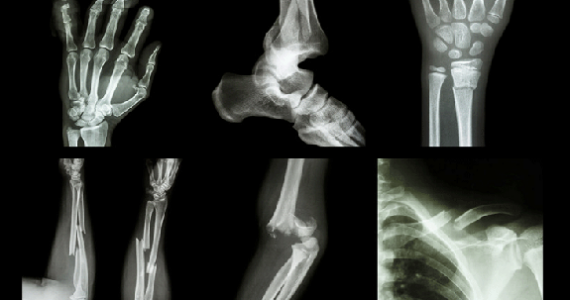

Localizarea si diagnosticul traumatismului se realizeaza in mod principal cu ajutorul radiografiei. Sunt si cazuri in care se recomanda suplimentar efectuarea unui Computer Tomograf sau RMN. Specialistul radiolog, in urma studierii filmului radiografiei, va putea oferi o interpretare imagistica concludenta relevanta pentru medicul specialist in ortopedie.